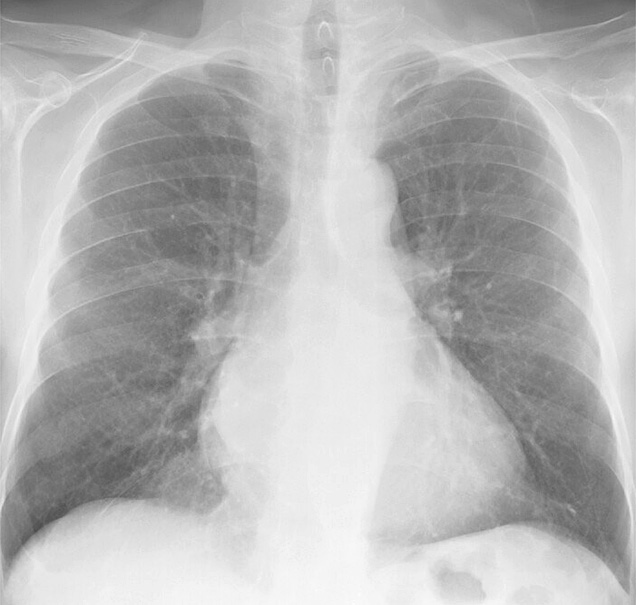

Gallery Cardiac Mitral Valve Disease Mitral Valve Disease Case 1 PA

Mitral Valve Disease

Case 1 PA